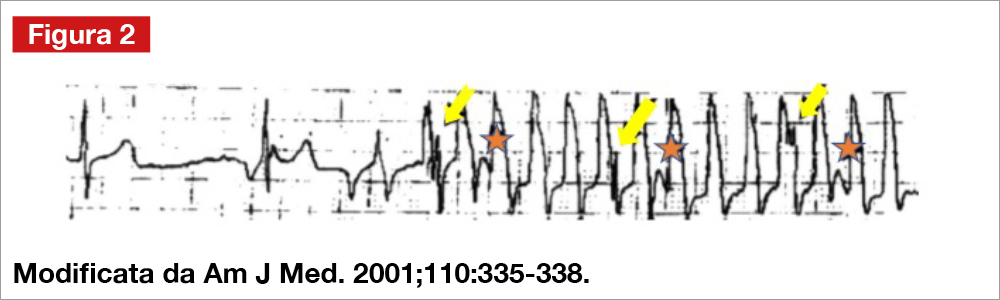

- i primi tre complessi QRS della registrazione, nei quali è presente un ritmo sinusale, appaiono riconoscibili sovrapposti agli apparenti QRS allargati (vedi frecce, Figura 2).

L’artefatto può essere stato causato da movimenti del corpo, ridotto contatto pelleelettrodo, allentata connessione dell’elettrodo, derivazioni malfunzionanti, miopotenzali etc… La problematica di artefatti durante registrazione Holter non è infrequente, così come il mancato riconoscimento dell’origine tecnica di essi: Knight e coll. hanno mostrato un tracciato Holter che mostrava una apparente TV a cardiologi, internisti ed elettrofisiologi. Una interpretazione non corretta della registrazione (TV) è stata posta dal 94% degli internisti, il 58% dei cardiologi e dal 38% degli elettrofisiologi[1]Knight BP, Pelosi F, Michaud GF, SA, Morady F. Physician interpretation of electrocardiographic artifact that mimics ventricular tachycardia. Am J Med. 2001;110:335–338. … Continua a leggere. Nella Figura 3, tratta dal lavoro originale di Knight e coll., le frecce gialle mostrano la sovrapposizione dei QRS sinusali al tracciato artefattuale, mentre le stelle rosse mostrano la sovrapposizione delle onde T. Nel paziente in esame, l’interrogazione del defibrillatore ha mostrato effettivamente la presenza di shock inappropriati, causati da parossismi di fibrillazione atriale verosimilmente condotti con aberranza.